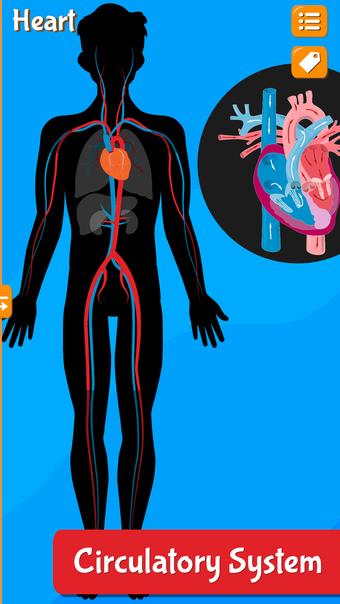

Anatomix es un juego de aprendizaje de anatomía humana que te enseñará a identificar todos los huesos del cuerpo humano y te permitirá explorar cada sistema en detalle. A medida que explores cada sistema, podrás identificar todos los huesos, músculos y otras estructuras.

Además de eso, podrás utilizar los diferentes huesos para identificar los diferentes sistemas.

La aplicación también te ayudará a identificar los diferentes huesos de tu propio cuerpo y te permitirá explorar cada sistema en detalle.